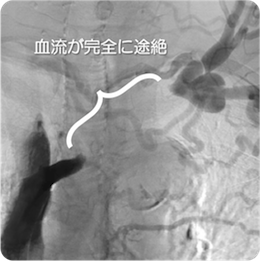

治療後

血管造影

左腸骨動脈が完全閉塞しており、左下肢の冷感、痛みを認めました。ステントを留置しいずれの症状も消失しています。